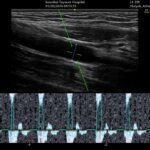

〇シャントエコー:定期的なエコー検査を実施し、透析の命綱である「シャント」のトラブルを早期発見・早期治療につなげます。